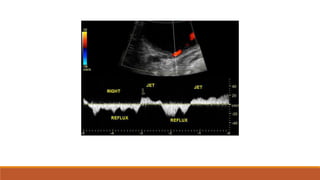

Reflux nephropathy

• Most cases secondary to vesicoureteral reflux (VUR)

Urinary bladder shows internal echoes.

Color Doppler shows vesicoureteric reflux.

Reflux